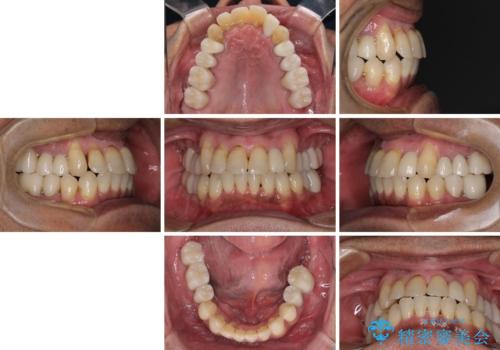

全体的に中等度の歯周病と診断されたため、歯周外科処置やインプラントによる咬合回復から進めて行き、矯正治療による歯列改善を行った後にオールセラミッククラウンにて補綴することとしました。

歯槽骨の再生治療を行ったため、外科処置後の静置期間がながくなり、4年弱の治療期間となりました。

初診来院時には矯正治療を行うことは想像していなかったようで、治療後には咬みやすさだけでなく、前歯が大変審美的に仕上がり、患者様には大変満足していただきました。